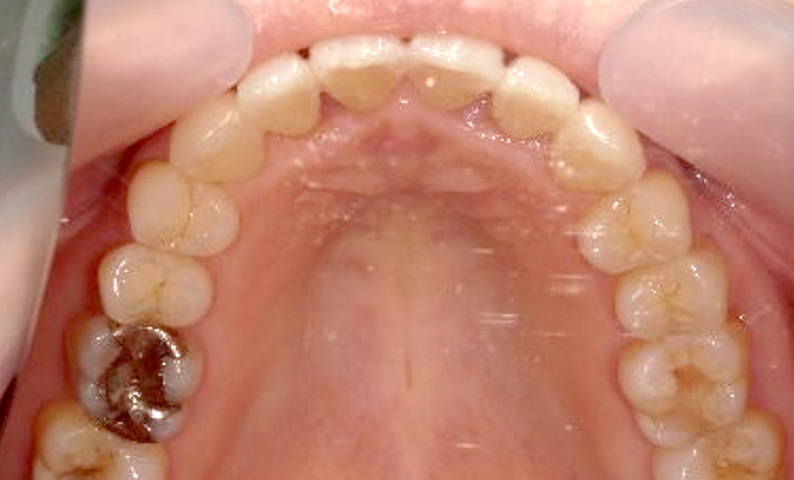

症例_001 上下顎の部分矯正

治療期間:12ヶ月金額:54万円+税女性反対咬合前歯のガタガタ

| Before | After |